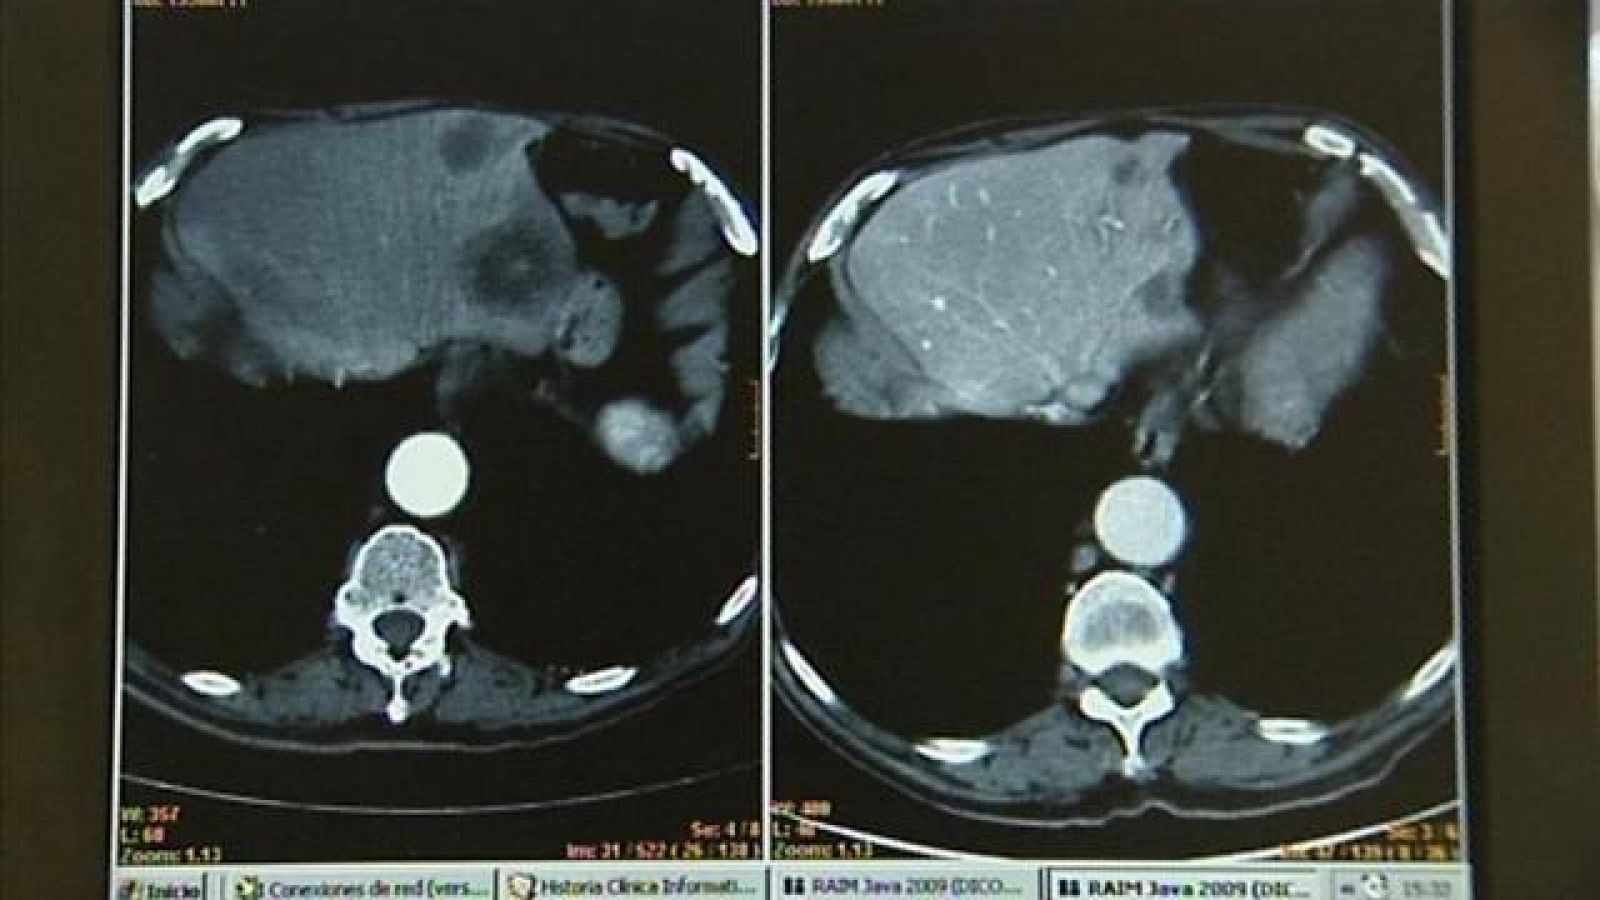

Según el último informe de la Sociedad Española de Oncología Médica paedecerán en un futuro la mitad de los hombres y una de cada tres mujeres. En Canarias, cada año se diagnostican casi 6.900 nuevos casos de cáncer. Hoy es el Día Mundial contra esta enfermedad.